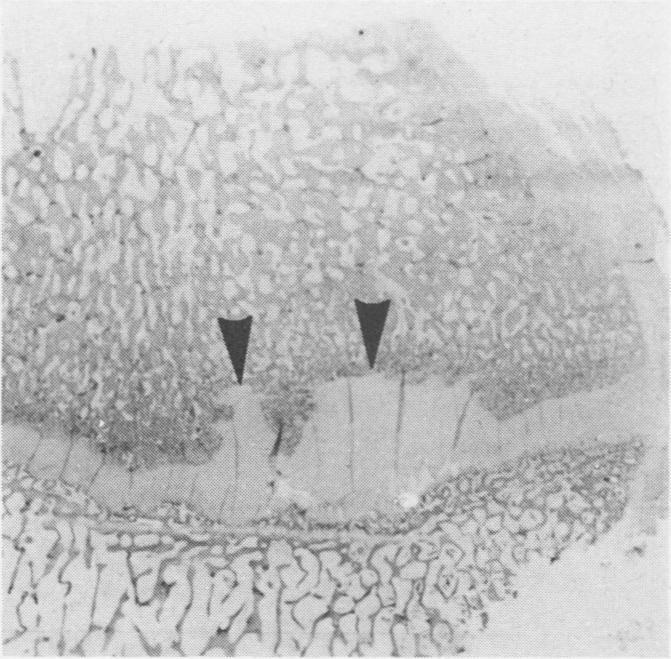

加拿大曼尼托巴省中北部地区犊牛的铜缺乏症

Copper deficiency in calves in northcentral Manitoba.

Four seven month old Simmental calves were examined because of unthriftiness, a persistent cough, stiffness and lameness. The calves had gastrointestinal and pulmonary parasitism. Analysis of the blood copper levels of these calves and of cows and calves on the farm indicated a generalized deficiency. Only the calves affected with parasitism showed signs of clinical copper deficiency.

对4头7月龄西门塔尔犊牛进行了检查,这些犊牛出现生长不良、持续咳嗽、僵硬和跛行症状。这些犊牛存在胃肠道和肺部寄生虫感染。对这些犊牛以及该农场的母牛和犊牛的血铜水平分析表明存在全身性缺乏。只有受寄生虫感染的犊牛表现出临床铜缺乏症状。